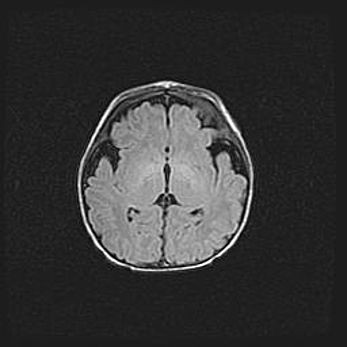

Множественные кисты обоих полушарий головного мозга, наибольшая из них в правой затылочной области. Ассиметричная атрофическая гидроцефалия.

Возраст: 7 месяцев

Вес: 5660 г

Пол: мужской

Окружность головы: 41,5 см

Срок гестации: 28-29 недель

Кисты головного мозга развиваются в результате многоочаговых некрозов вещества мозга и возникают вследствие перенесенной перинатальной инфекции, менингитов, энцефалитов, асфиксии, родовой травмы, расстройств мозгового кровообращения различного генеза. Образованию кист в веществе головного мозга плодов и новорожденных способствуют такие факторы, как высокое содержание в нем воды, недостаточная (или отсутствие) миелинизация и слабая астроглиальная реакция на повреждение.

Кисты могут сочетаться с гидроцефалией и другими поражениями головного мозга.